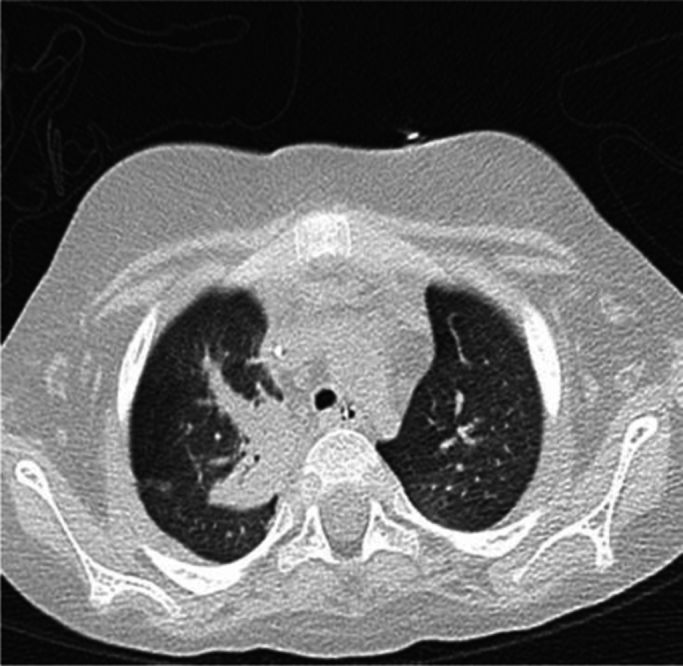

Fig. 3.

CT scan revealed lesions compatible with IA.